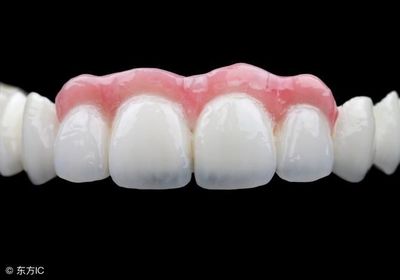

烤瓷牙是现在流行的一种牙齿,可以让你的黄牙洁白如雪。这也赢得了很多朋友的喜爱。毕竟,洁白的牙齿不是让每个人都幸运的。烤瓷牙可以有效帮助牙齿看起来更健康。那么烤瓷牙需要注意什么呢?接下来我会详细告诉你什么是烤瓷牙,烤瓷牙有什么危害,烤瓷牙有什么不适。什么是烤瓷牙?烤瓷牙是固定义齿的一种,内层是金属。

颜色非常接近人类牙齿的本来颜色。患者不能自行摘下,而是用水泥粘在磨好的牙齿上。瓷层颜色可根据患者邻牙颜色进行搭配,修复后美学效果一般较好。烤瓷牙口腔异味的危害由于烤瓷牙与真牙之间密封不彻底,食物残渣容易残留在牙齿内,牙齿内细菌代谢产生异味,容易形成口臭。受不了忽冷忽热* * *在医生配牙的过程中,牙医不小心磨坏了牙齿。